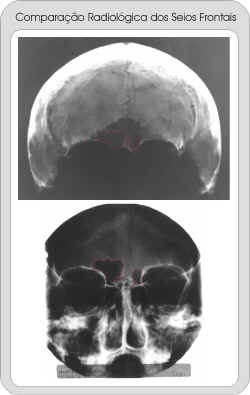

Identificação Humana por Comparação Computadorizada de Imagens Radiográficas dos Seios Frontais

espaco2.gif (821 bytes)Radiografia da calvária, um dos poucos ossos disponíveis ao exame pericial.

espaco2.gif (821 bytes)O osso frontal estava fraturado com perda de substância da tábua vestibular na região dos seios frontais, expondo-os. Por esta razão a imagem obtida dos mesmos foi de  baixa qualidade, porém suficiente para uma identificação.

espaco2.gif (821 bytes)Radiografia em incidência para seios da face obtida intra-vitae do suspeito e enviada ao Laboratório de Antropologia Forense para confrontação.

espaco2.gif (821 bytes)Observe a peculiar anatomia dos seios frontais com notável assimetria.